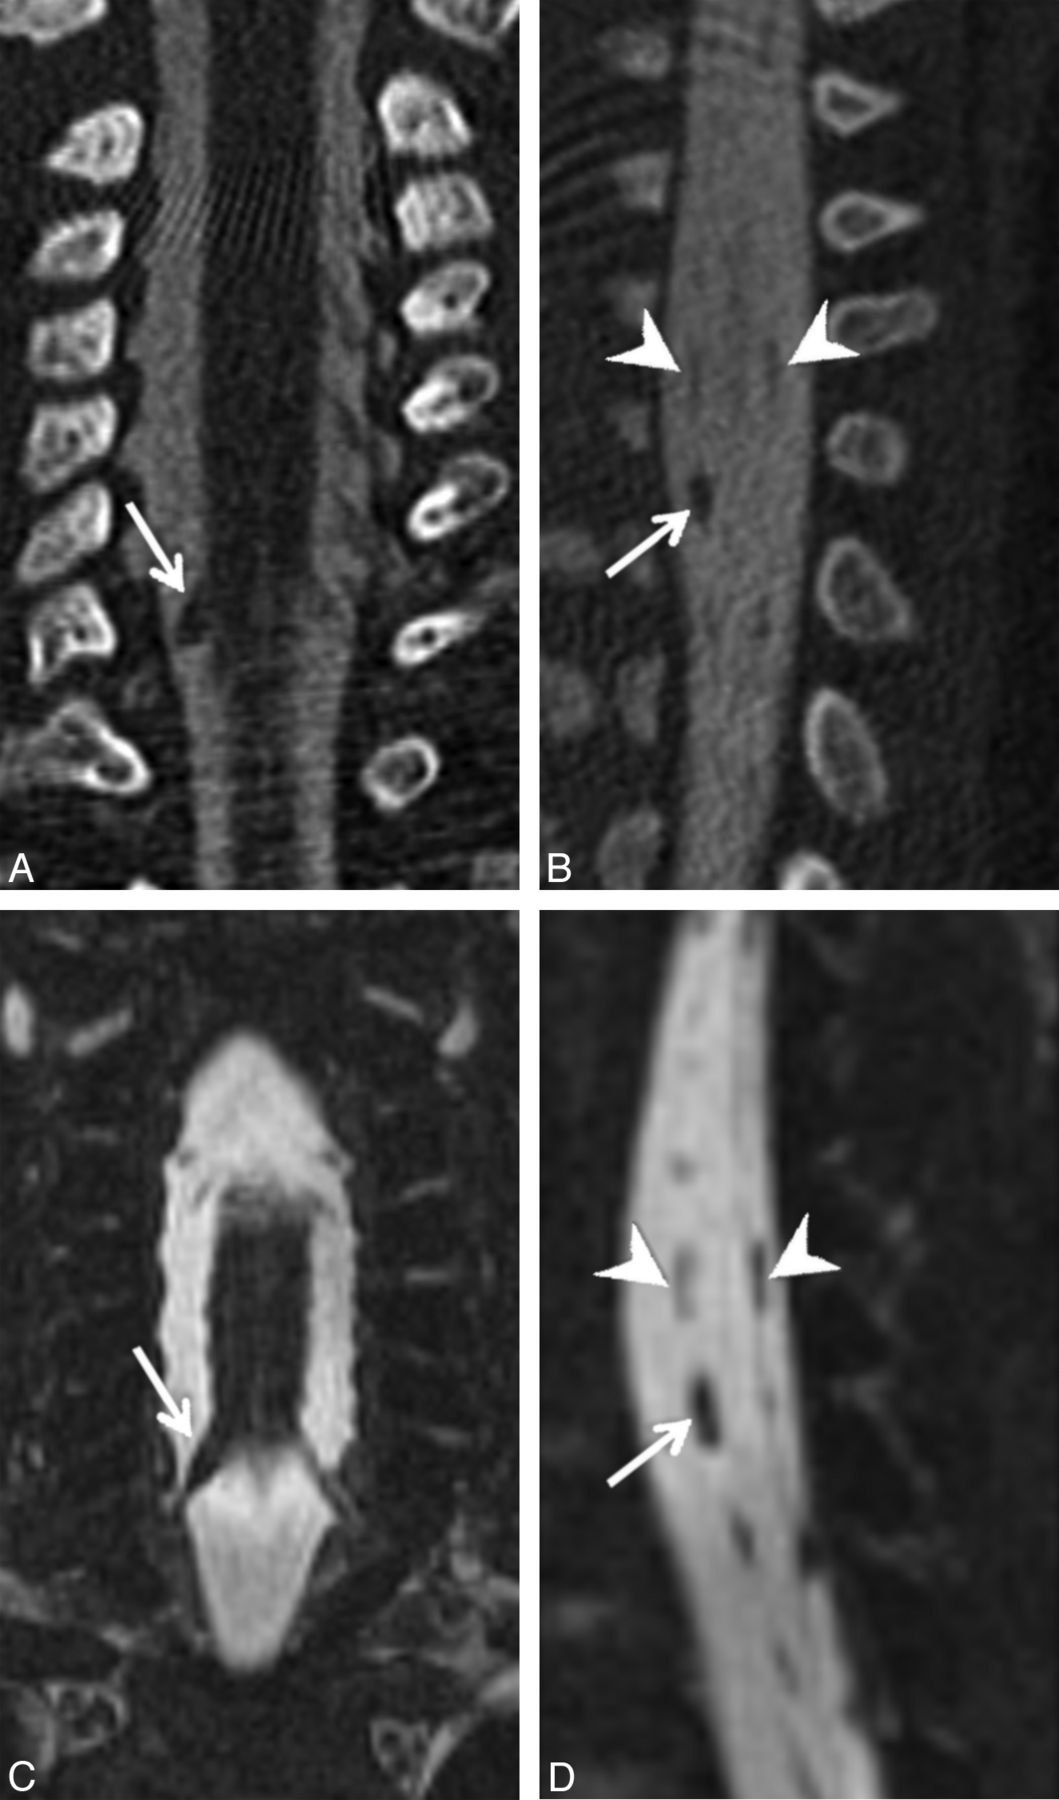

Axial (A), coronal (C), and left parasagittal (E) images from a CT myelogram and corresponding axial (B), coronal (D), and left parasagittal (F) images from an MR myelogram (B, D, and F) on the same patient demonstrating 3 consecutive left-sided pseudomeningoceles with absent rootlets at C7–T1 (arrows in A and B, arrowheads in C and D, arrows in E and F). Note the internal septa within the middle and lower pseudomeningoceles that can simulate intact rootlets on a single image.